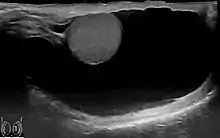

Prin diagnosticarea cu ultrasunete acumularea de lichide poate fi evidențiată corect.